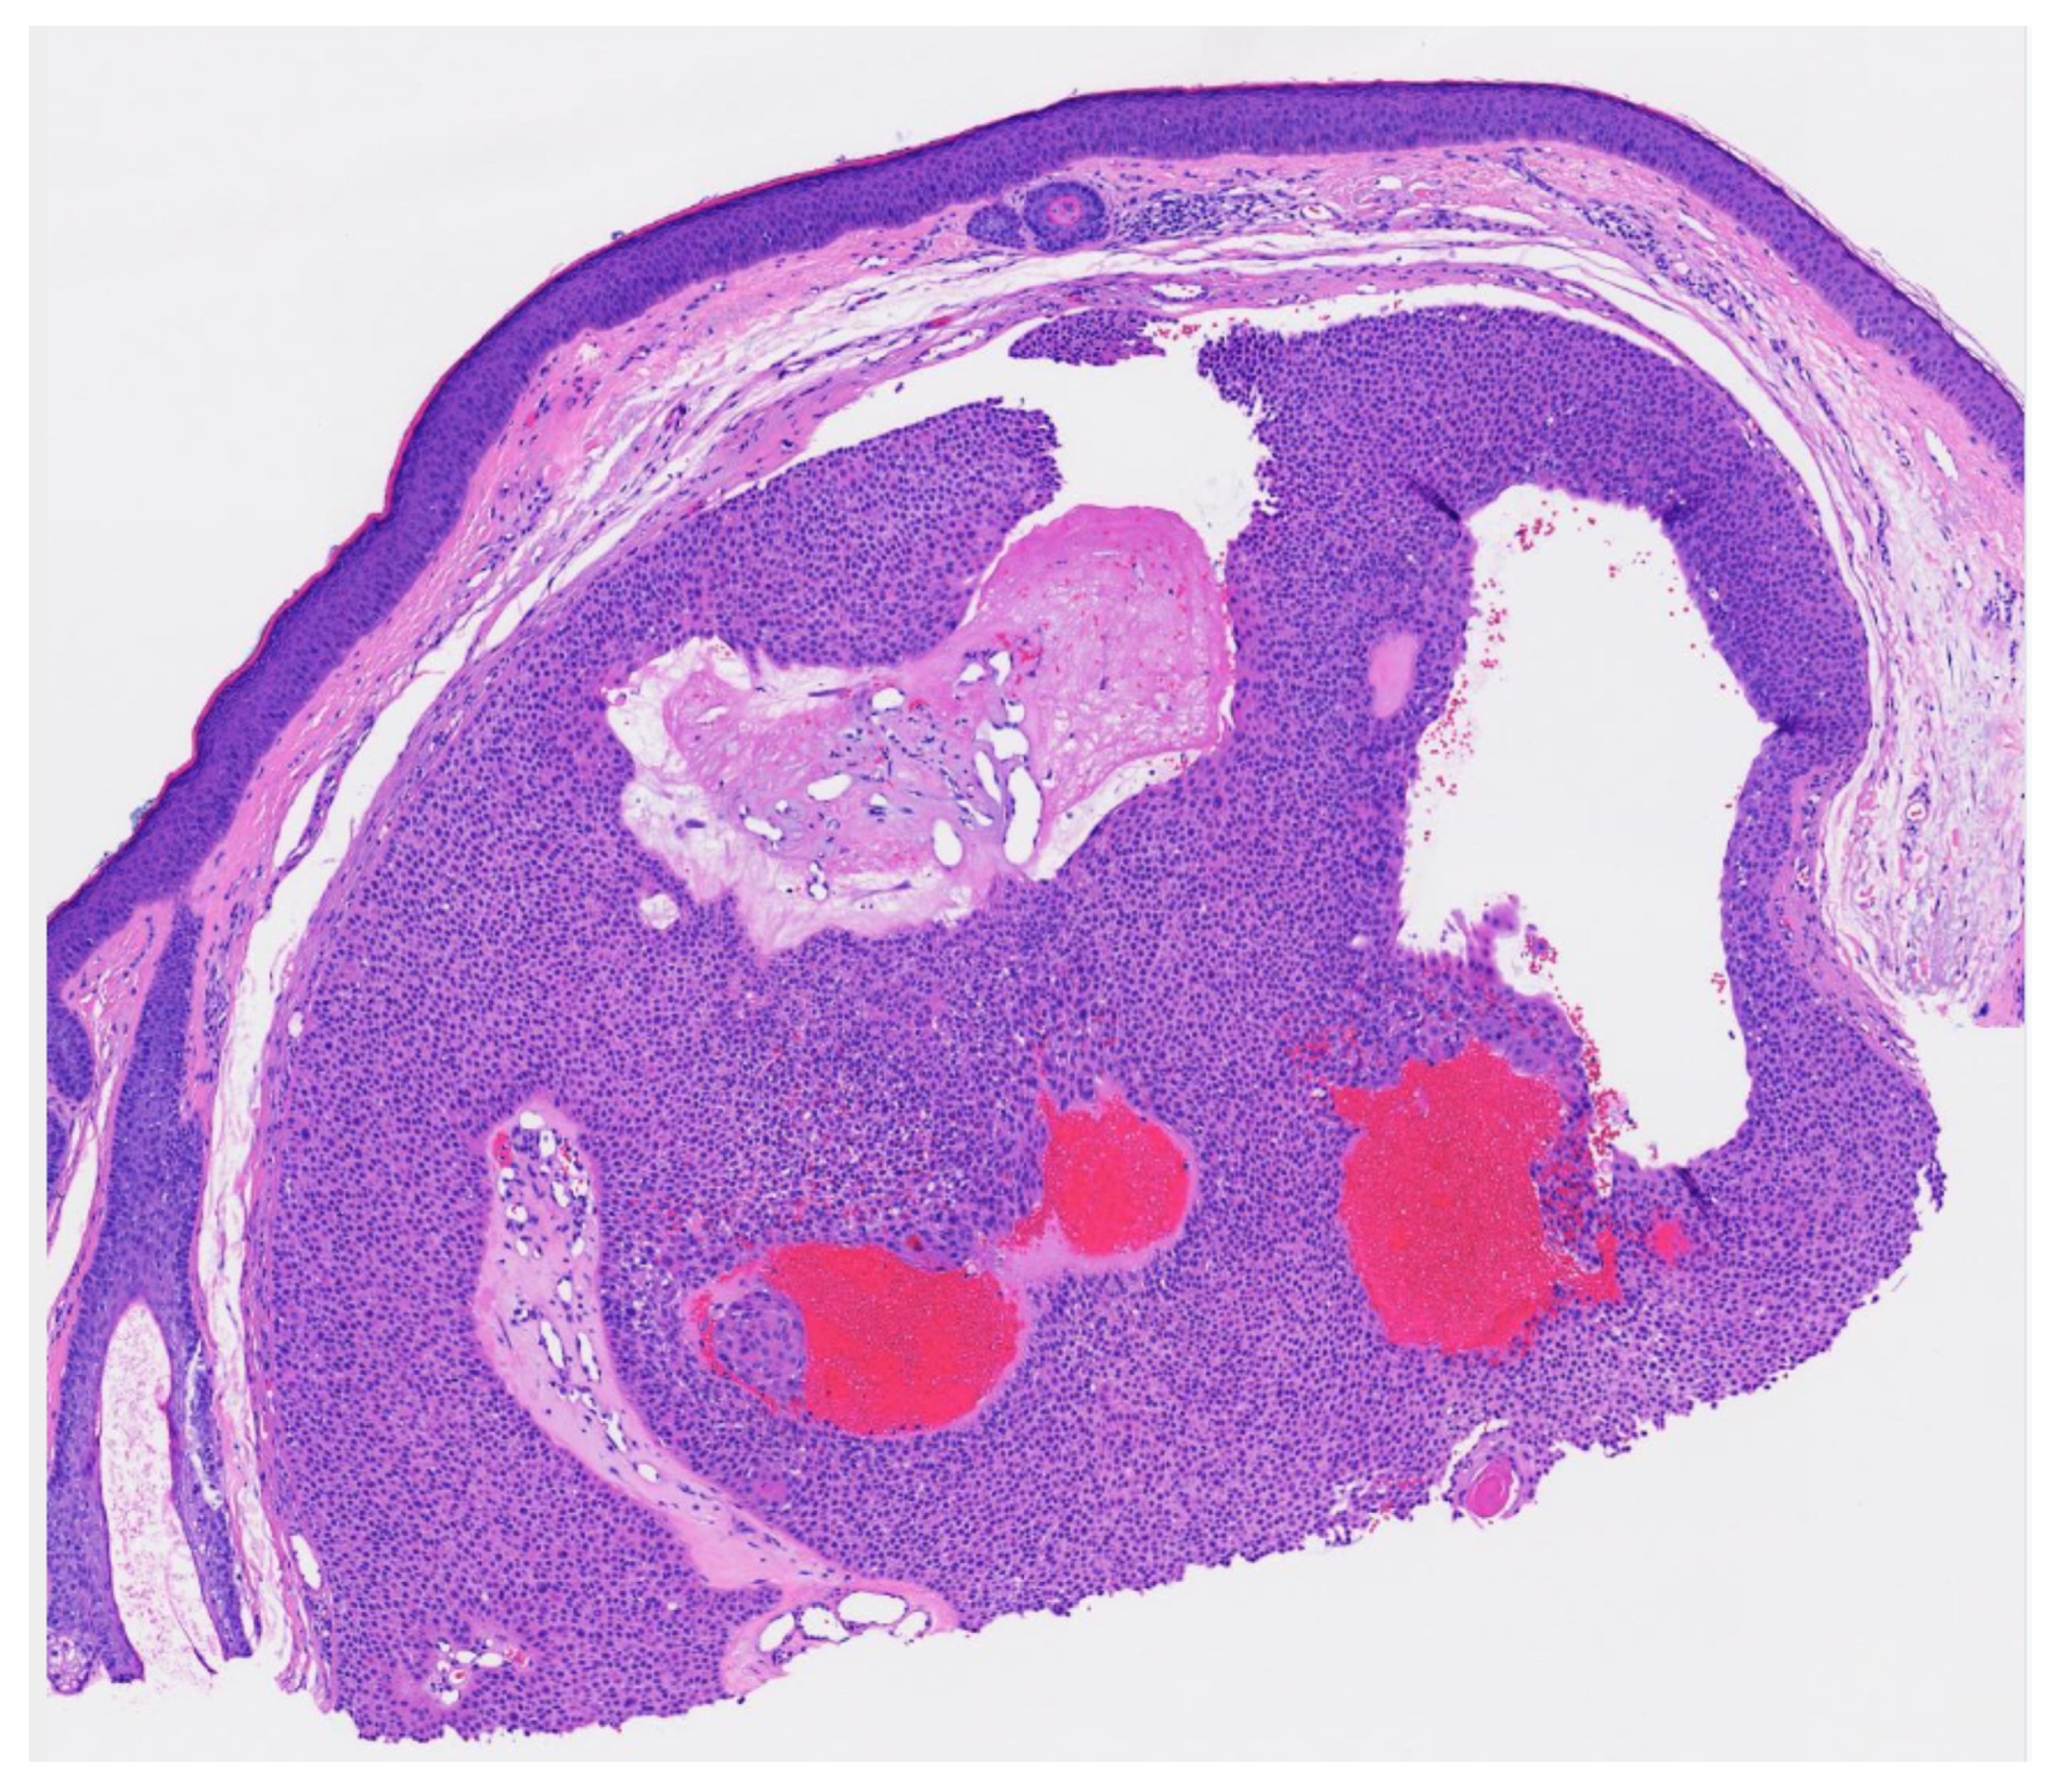

Figure 5. Residual DDT on punch excision (from the transected spiecimen in Figure 3) (H & E, 10×).

Figure 3. Well circumscribed, dermal-based, solid and cystic tumor with no connection to the overlying epidermis (H & E, 2×).

Poroma variants are differentiated based on the predominant cell type present and the degree of epidermal/dermal involvement [2]. However, multiple variants can exist within the same lesion. DDTs are primarily confined to the superficial dermis and are composed of small solid and cystic nodular aggregates of poroid, cuticular, and clear cells (Figure 3, Figure 4 and Figure 5) [2]. Eccrine poromas are also composed of all three cell types, but are primarily located in the epidermis and superficial dermis. Hidroacanthoma simplex is mainly composed of poroid cells, less cuticular cells, and no clear cells [2]. It is confined to the epidermis. Poroid hidradenoma contains a mixture of all three cell types and is also confined to the dermis [2]. In contrast to DDT, poroid hidradenomas have large aggregates of solid and cystic components and extend deeper into the reticular dermis and even subcutis [2].

The histopathologic diagnosis of DDT is rare due, in part, to the fact that some regard DDTs as poromas with a limited epidermal connection that has not been identified on the histologic sections examined or as hidradenomas that are smaller and more superficial [30]. As an example, Figure 3 may be regarded by some as representing a hidradenoma. This controversy in the histopathologic classification of poroid neoplasms without clear-cut evidence for the clinical significance of distinguishing these lesions from each other has given rise to the thinking that the poroma classification scheme may just be a matter of semantics [19]. This has led to some pathologists diagnosing these lesions under the overarching term as “acrospiroma” only without further classification.